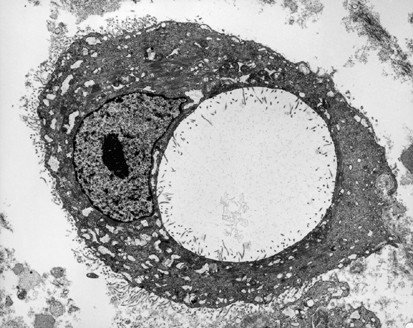

Figure 5

Mesothelioma cell with intracytoplasmic lumen. Microvilli can be seen along the cell membrane and the membrane limiting the lumen. Bundles of intermediate filaments are also apparent in the cytoplasm (× 4400).